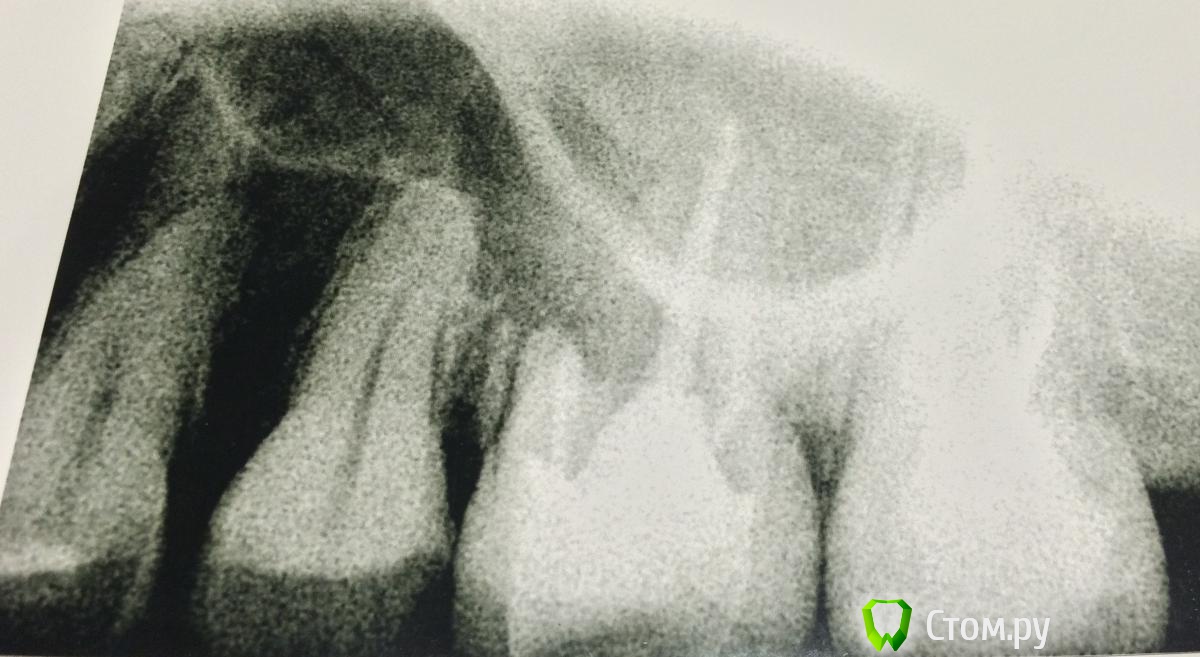

OlgaSm Опубликовано 9 ноября, 2014 Автор Поделиться Опубликовано 9 ноября, 2014 (изменено) А вот и снимок. На нем 7, 6, 5 и часть 4 зуба. 8-ка удалена несколько лет назад. Если удалять / лечить - то какой? Огромное человеческое спасибо! Изменено 9 ноября, 2014 пользователем OlgaSm Ссылка на комментарий

Гарриевич Опубликовано 9 ноября, 2014 Поделиться Опубликовано 9 ноября, 2014 к сожалению по этому снимку ничего толкового сказать нельзя Ссылка на комментарий

kriokov Опубликовано 9 ноября, 2014 Поделиться Опубликовано 9 ноября, 2014 Снимок к сожалению мало информативен.То, что Вы описываете не совсем укладывается в клинику ОДОНТОГЕННОГО гайморита, по клинике более тянет на риногенный.Что делать1. обязательно закончить лечение у Лора, это даст улучшение, и часто на довольно значительный временной период, 2. благополучно родить малыша3. После предметно обследоваться и у лора и у стоматолога с применением всех современных доступных методик, втом числе и клкт4. по необходимости лечения зубов именно сейчас-- сложно сказать по такому снимку, но склоняюсь к тому, что этот гайморит не от зубов 5 Ссылка на комментарий

samsonov Опубликовано 10 ноября, 2014 Поделиться Опубликовано 10 ноября, 2014 С оочень большой натяжкой можно предположить некорректное пломбирование каналов шестого зуба...Вы снимок с экрана делали?Если да, то можно улучшить) изображение, скопировав непосредственно с компа визиографа. 2 Ссылка на комментарий

Dr.Sham Опубликовано 10 ноября, 2014 Поделиться Опубликовано 10 ноября, 2014 (изменено) И тем не менее, началось все с зубов, пятый зуб был в порядке, шестой и седьмой по снимку видно, что они в непосредственной близости к пазухе, шестерка депульпирована, на щечном медиальном можно заподозрить воспаление даже по этому снимку, щечного медиального второго не видно - это классика, что не нашли MB2, с семеркой не понятно по снимку, депульпирован или нет.Необходимо взять выписку из карточки по лечению (депульпированию) 6 зуба. Я уверен, что там будет написано: найдено 3 канала, значит, что четвертый пропущен. и 7 зуба - с ним непонятная картина.Если все так, как я говорю, то причина в 6-м, значит коронку нужно снимать, оценить состояние твердых тканей зуба, если что-то от зуба осталось - есть за что бороться (у врачей есть четкие критерии), то лезть в каналы и искать четвертый. Если от зуба ничего не осталось, то удалять зуб.Врача нужно искать, который работает с микроскопом. Изменено 10 ноября, 2014 пользователем Dr.Sham 1 Ссылка на комментарий